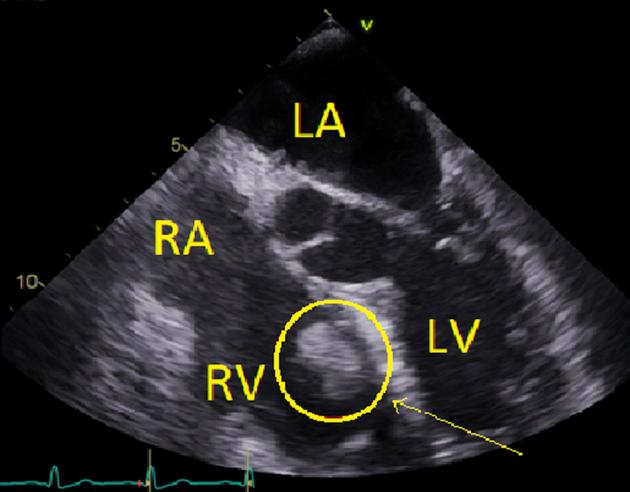

肾细胞癌伴右心室转移扩散:一项预后不良的罕见发现。

Renal Cell Carcinoma with Right Ventricular Metastatic Spread: An Unusual Finding with Poor Prognosis.

• RCC is the most common type of renal cancer. • RCC is capable of passing through the renal vein into the IVC. • Surgical resection requiring cardiopulmonary bypass is currently the only curative treatment. • Metastatic RCC tumor spread into the heart is a poor long-term prognostic factor.

摘要

• 肾细胞癌是最常见的肾癌类型。

• 肾细胞癌能够通过肾静脉进入下腔静脉。

• 目前需要体外循环的手术切除是唯一的治愈性治疗方法。

• 转移性肾细胞癌肿瘤扩散至心脏是一个不良的长期预后因素。